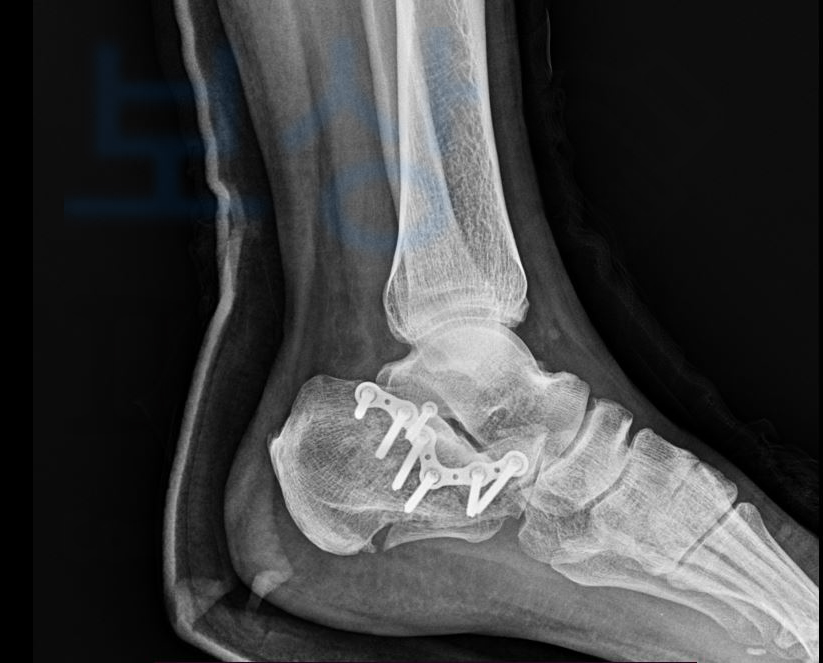

위 사고로 인해 엑스선상에 보이는

발 뒤꿈치 뼈의 골절 즉

좌측 종골의 분쇄골절 s92

진단을 받아 핀고정 후 최소 전치 8주 요양이 필요하셨습니다. 저희는 먼저 고객님의 보험가입 시점과 약관을 파악하기 위해 보험증권을 요청해 분석하였습니다. 이후 진단서, 영상CD, 의무기록등을 받아 환자의 장해상태 내에 적정한 보상 범위를 예상하여 안내를 드렸는데요, 저희의 십수년 경력과 자신있는 상담에 믿고 맡길 수 있다는 생각이 들어 후유장애 청구를 맡겨주셨다고 합니다.